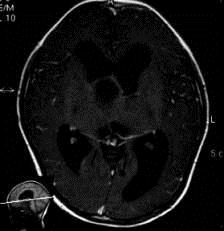

问题 病历摘要:??患者女性,6岁,半年来感觉视力模糊,近10天出现反复头痛,间有恶心呕吐,精神转差,查体:神志清楚,身高90cm,体重25Kg,血压90/55mmHg,右眼视力4.6,左眼视力4.8,双侧视乳头水肿,颈软,伸舌居中,四肢肌张力正常,肌力5级,双侧Babinski征(-)。 患者入院第三天,安排手术治疗,请选择最适用的手术入路。

选项 A.额下入路 B.翼点入路 C.终板入路 D.经胼胝体入路 E.经蝶窦入路 F.翼点-经胼胝体联合入路 G.额下-翼点联合入路 H.经脑室入路

答案 BF